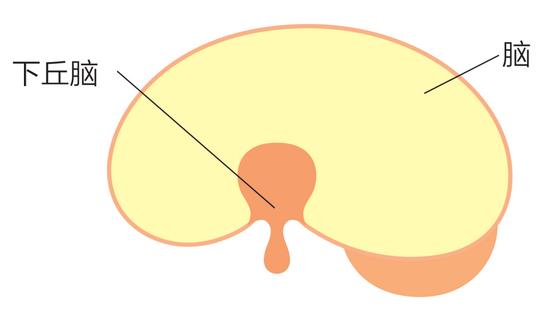

女性激素分泌的司令塔

激素的枢纽和自律神经的枢纽,

都在大脑的相同位置。

因此女性激素减少的话会产生

脑的下丘脑有自律神经系统、内分泌系统(激素分泌)的中枢。

更年期症状是由女性激素剧减引起的。在妇产科的瑜伽教室高尾美穗副院长说:“卵巢功能低下女性激素减少的话,分泌女性激素与向卵巢发出指令的脑下丘脑会陷入混乱。其余波还会波及该下丘脑负责的自律神经系统,那么不仅仅是上火、潮红这些内分泌系统紊乱的症状,还会引起焦虑及疲劳等这些自律神经的症状。